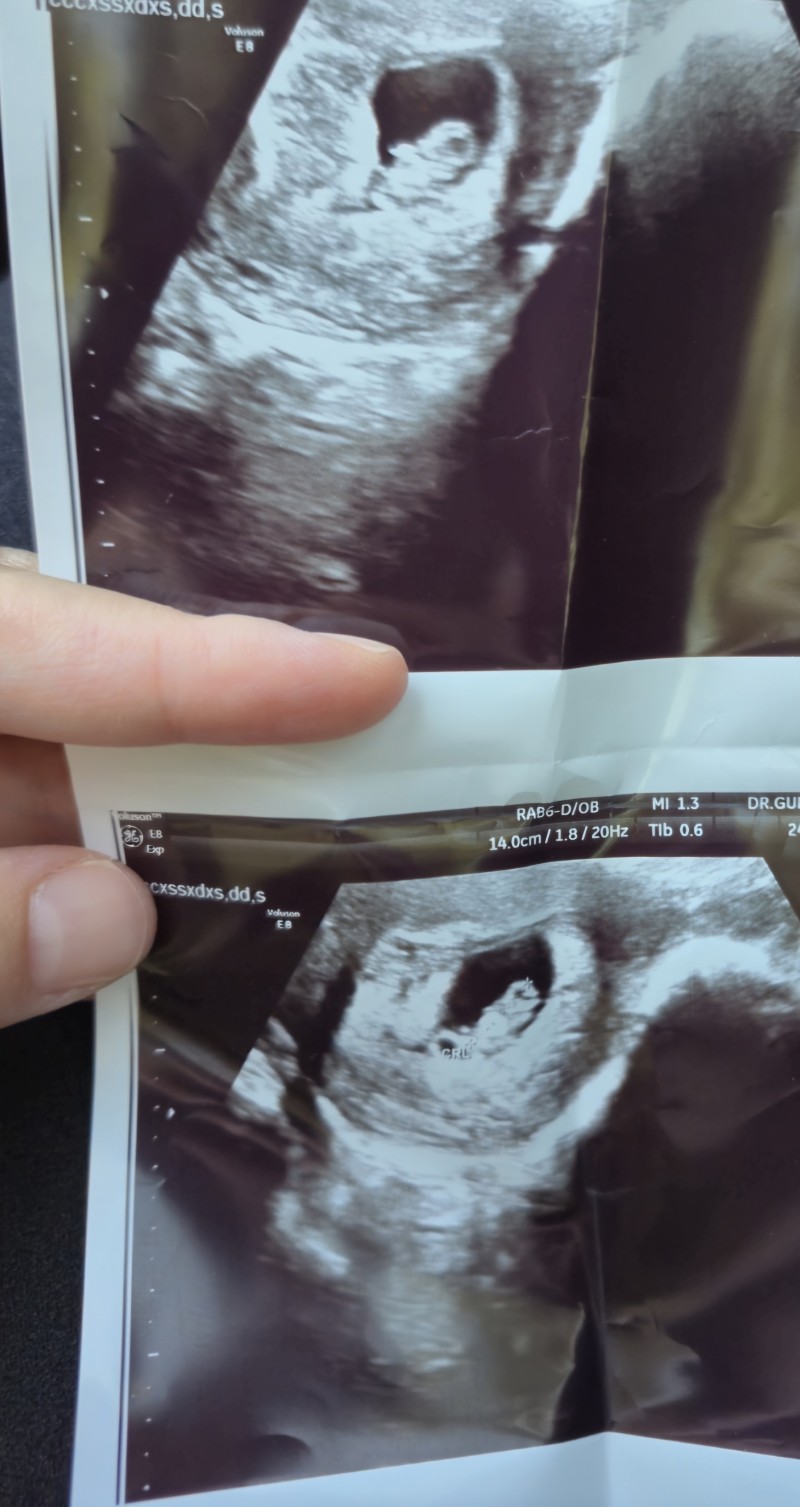

Cinsiyet tahmininde bulabilecek olan var mı

Bence kız... Benım ilk evladım kızdı kesesı yuvarlaktı bu sekılde.. Sımdı hamıleyım bu da erkek. Onun kesesı bıraz daha yatsı ve sekıllı gıbı. Hatta oğlana hamile kaldığımda ilk ultrason kagıdını karsılastırmıstım acaba erkek mı demıstım erkek çıktı. Yıne de  bu tahmın tabıkı. Bılemem.

Keseden degilde kafa seklinden kiz gibime geldi. Ogrenince yazarsin☺️

Boyle olunca kiz diyolar.kese şekilli sükulluyse erkekmiş. Benimki erkekti ciddende boyle duzgun değilde

Benim iki kızımda da yuvarlaktı ona benzettim bende ama benimki tam yuvarlaktu

benim tecrübeme göre kız diyorum çünkü kız bebeğimde kese düzgün yuvarlaktı erkek bebeğimde fasulye gibi genişti gülücüge benziyodu doktora sormuştum hatta niye böyle diye normal demişti ozmn erkek galiba çok değişik kese şekli diye düşünmüştüm öylede oldu herkeste farklı olur tabi bilemem bu benim aşırı ultra bilimsel fikrim ahahahahah